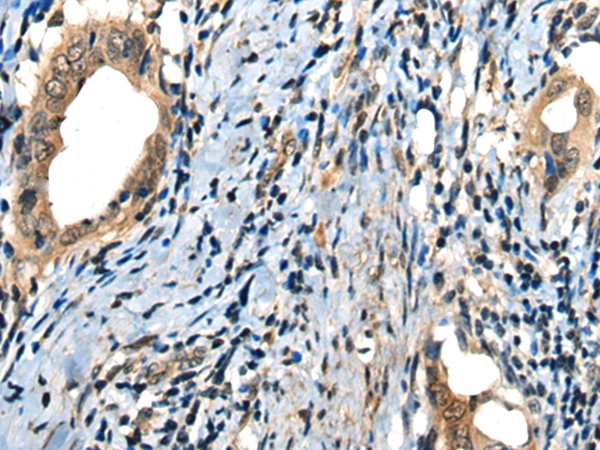

The image on the left is immunohistochemistry of paraffin-embedded Human thyroid cancer tissue using 46612(MICU1 Antibody) at dilution 1/35, on the right is treated with fusion protein. (Original magnification: x200)

The image on the left is immunohistochemistry of paraffin-embedded Human cervical cancer tissue using 46612(MICU1 Antibody) at dilution 1/35, on the right is treated with fusion protein. (Original magnification: x200)